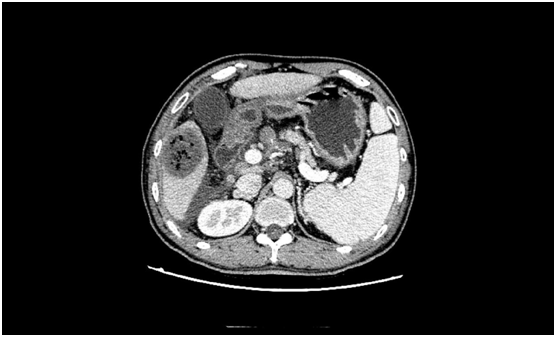

術(shù)前發(fā)現(xiàn)患者的肝臟5段有一個5.5cm大小的惡性腫瘤,此外還有大量腹水、門脈高壓癥、脾功能亢進(jìn),同時合并有消化道出血、肝功能差等癥狀。而在患者的肝臟7段,亦存在一個2cm大小的肝內(nèi)轉(zhuǎn)移灶。

術(shù)后復(fù)查CT見腫瘤全部失去了活性